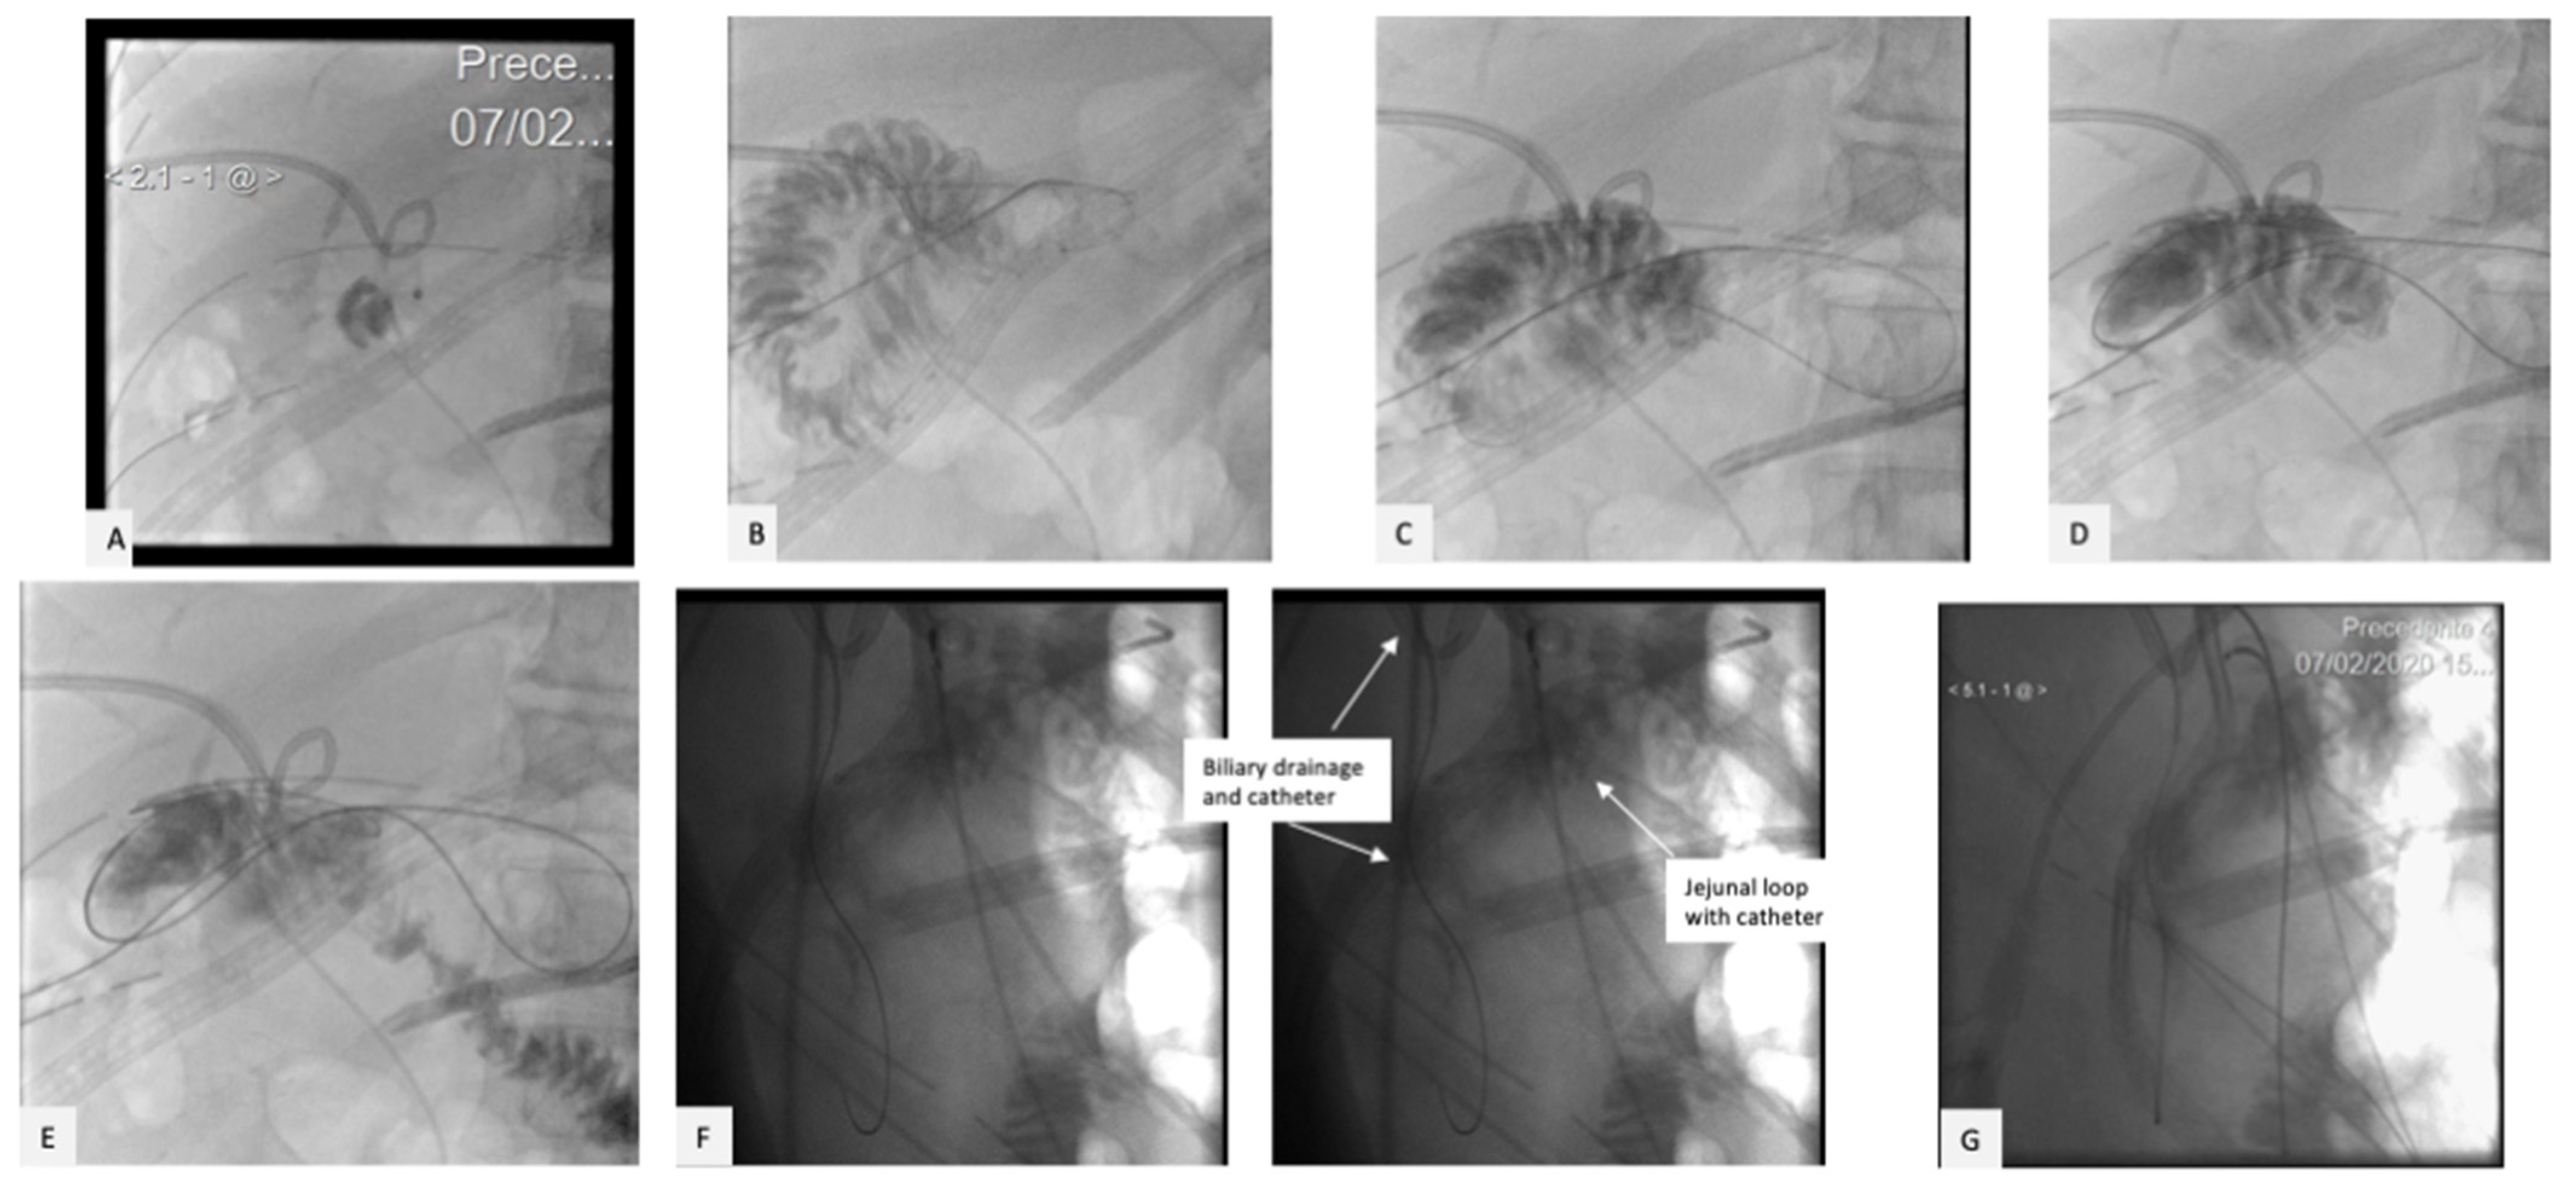

2. Case Presentation